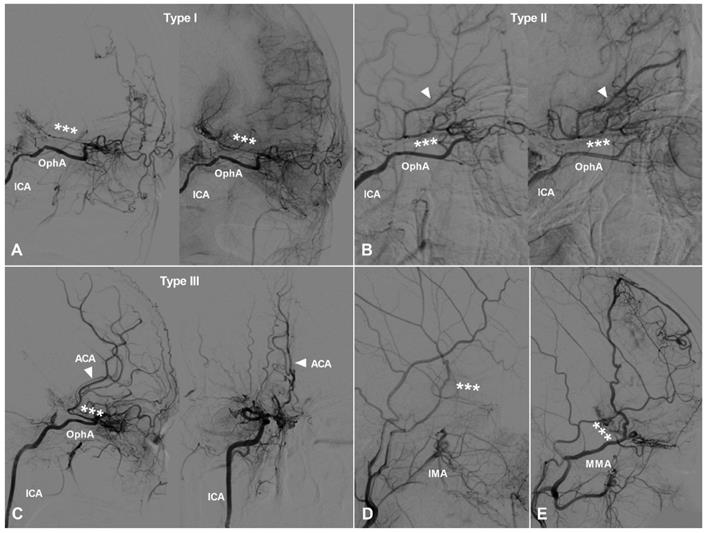

Collaterals from the posterior circulation to the frontal lobe

Most of the time, arteries in the posterior circulation are not involved in patients with MMD and can provide compensating collaterals to the anterior circulation [4]. These collaterals mainly comprise of callosal circle, ventricular collaterals, and cranial base collaterals [1]. These collaterals are illustrated in Figure 5. As the posterior communicating artery (PComA) and anterior choroidal artery (AChA) could also participate in the posterior to anterior compensation [10, 11], enlargement of the the PComA and AChA was also evaluated in this study.

Figure 5

Collaterals from the posterior circulation. A, Angiogram of the VA in lateral view shows the PCA and PChA anastomose with the posterior portion of the ACA (asterisks), forming a callosal circle. In addition, ventricular collaterals (arrow heads) could also be noted in this patient. B, Angiogram of the VA in lateral view shows the posterior circulation provides blood supply to the territory of ACA via the PComA (arrow head). C, Angiogram of the VA in lateral view shows the posterior circulation provides blood supply to the territory of ACA via the moyamoya-like vessels (oval) at the cranial base. D, Angiogram of the VA in lateral view shows the posterior circulation provides blood supply to the territory of ACA (oval) via pial branches of the MCA, namely the PCA-MCA-ACA pathway. E, Angiogram of the VA in AP (left) and lateral (right) views shows moyamoya-like alteration in the posterior circulation. The posterior circulation could still provide collateral (asterisk) to the anterior circulation. F, Angiogram of the ICA in lateral view shows the PChA (arrow head) anastomoses with the PCA (asterisk) via retrograde blood supply. F, Angiogram of the ICA in lateral view shows the AChA (arrow head) anastomoses with the PCA (asterisk) via antegrade blood supply. Abbreviations: ACA, anterior cerebral artery; AChA, anterior choroidal artery; AP, anteroposterior; ICA, internal carotid artery; MCA, middle cerebral artery; PCA, posterior cerebral artery; PChA, posterior choroidal artery; PComA, posterior communicating artery; VA, vertebral artery.

Callosal circle

The posterior choroidal artery (PChA) and/or cortical branches of the posterior cerebral artery (PCA) could anastomose with the ACA at the posterior part of the corpus callosum and perfuse retrogradely to the territory of ACA, which is called callosal circle [12].

Ventricular collaterals

In rare circumstance, the posterior circulation could provide blood supply to the frontal lobe via the ventricular arterial network, which is called ventricular collaterals [13].

Cranial base collaterals

The posterior circulation could provide blood supply to the territory of ACA via anastomosing with bridging vessels at the cranial base. These bridging cranial base vessels mainly include the moyamoya-like network, the remnant PComA, and the cortical branches of middle cerebral artery (MCA) [14]. The complete collateral pathways are from PCA-MCA to ACA, from PCA-PComA to ACA, and from moyamoya-like network to ACA.